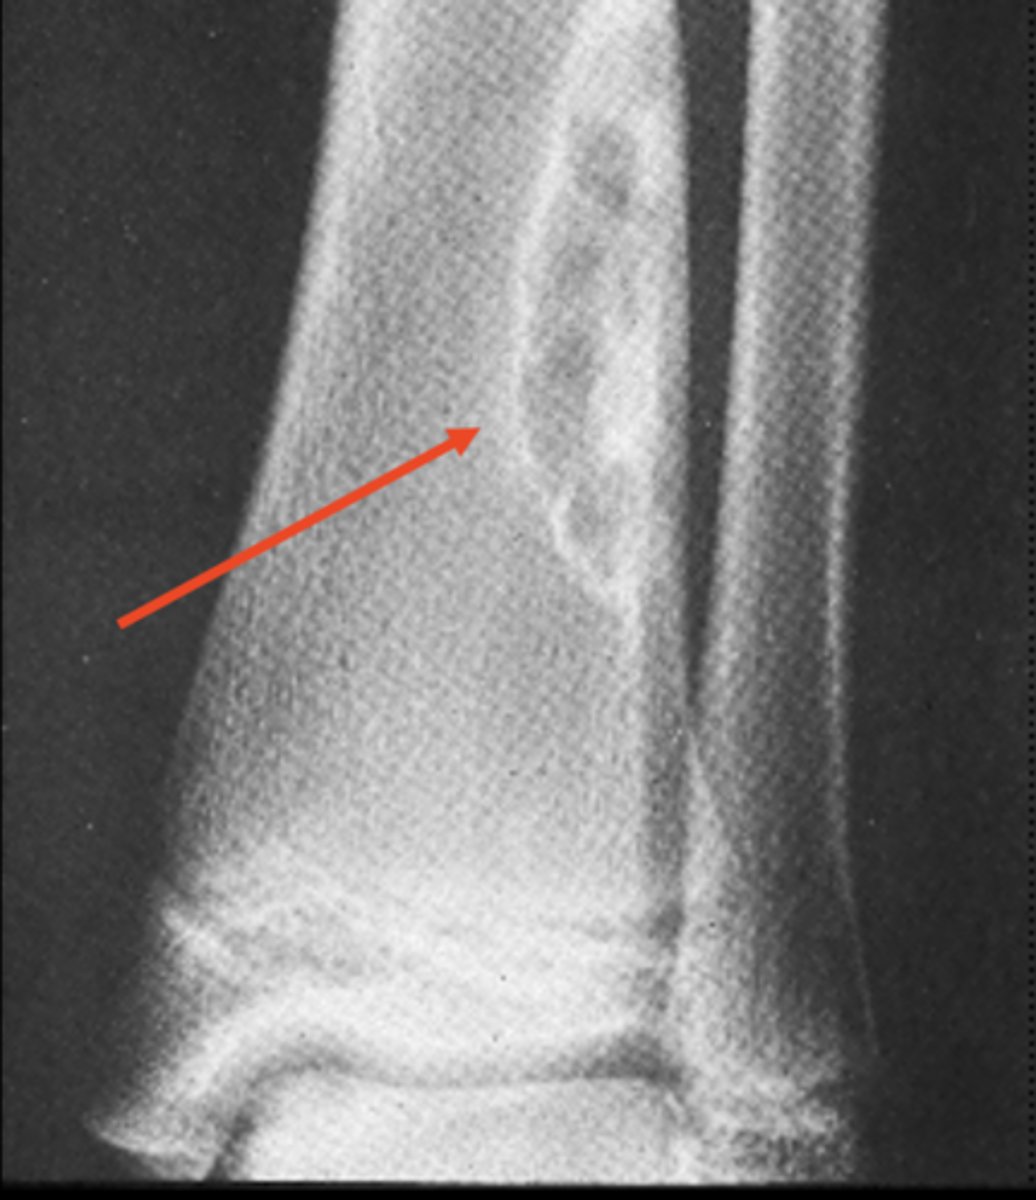

Nidus

ID radiographic feature of osteoid osteoma

<p>ID radiographic feature of osteoid osteoma</p>

- Central radiolucent nidus <1 cm

- Surrounding sclerosis

- Central calcific fleck

- Metaphyseal and diaphyseal

- Positive bone scan

State the radiologic features of osteoid osteoma

<p>State the radiologic features of osteoid osteoma</p>